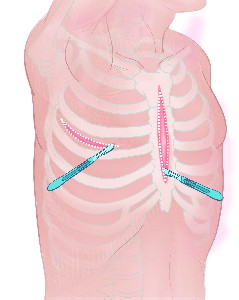

Detailreiche Fotografien aus der medizinischen Praxis ergänzen die Texte; moderne, genaue,

wissenschaftliche Zeichnungen geben Einblick in die Anatomie und die Funktion der Lunge und

anderer Organe.